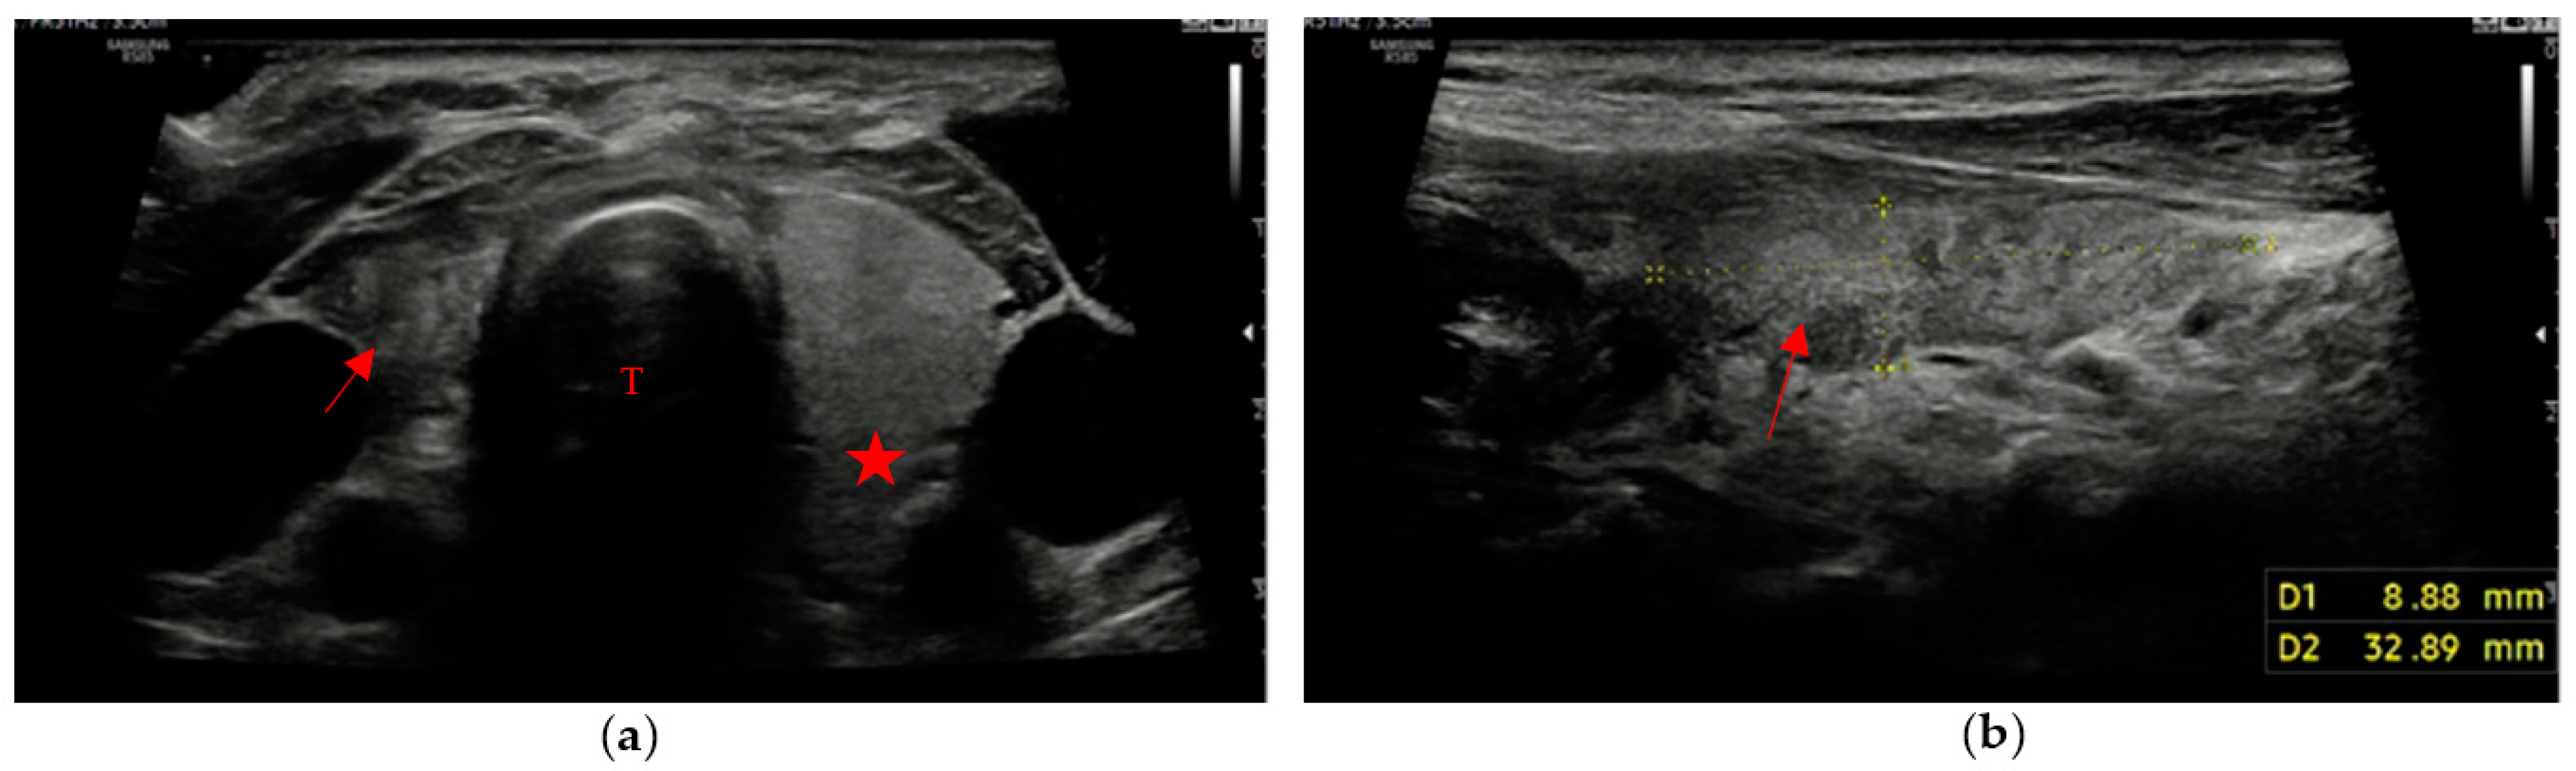

• A markedly hypoechoic pattern with well-defined margins, often with evidence of a peripheral halo (pseudo-capsule appearance), was found in 13 patients, which is approximately 34% of patients with evidence of residual swab (Figure 1a,b).

Figure 1. Residual swab pattern (red arrow) 1, characterized by a markedly hypoechoic pattern with an ecostructure of hyperechoic spots and well-defined margins; (a) Longitudinal view; (b) Axial view. Jugular vein (JV), Carotid artery (CA) and Trachea (T).